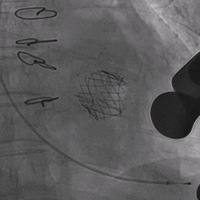

手术按照术前讨论方案进行,过程顺利,成功植入23号Renato®球扩瓣,瓣膜植入位置理想,启闭功能表现出色,左室造影及经食道超声反复观察无明显瓣中及瓣周反流。Renato球扩瓣植入后二尖瓣峰值流速降至1.37m/s,平均跨瓣压差降至3mmHg, 左室流出道峰值流速不到1.5m/s。术后患者即清醒,在手术间拔除气管插管,并送回心外科监护室,观察10余小时后,次日转回普通病房。

术前左室造影,可见二尖瓣瓣内大量反流 术后左室造影,无反流及瓣周漏